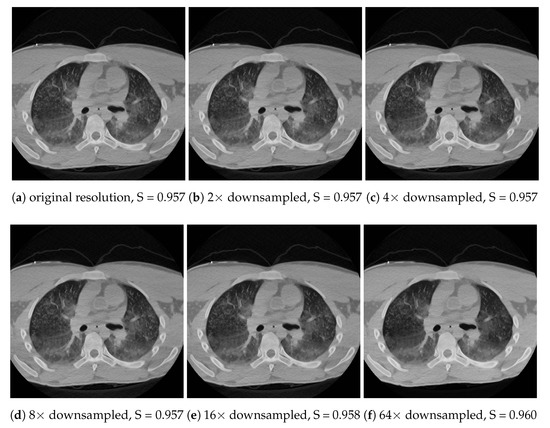

Both spatial downsampling and dithering build on the fact that important features in the images usually have a larger area than a few pixels, and the local histograms do not change too fast; therefore, the 3D histogram can be approximated well with one which has reduced resolution along all axes. As long as these assumptions are valid, the tone mapping can approximately linearly speed up with downsampling in terms of the number of pixels and/or shades. Memory consumption scales down in a similar manner. The effect of the techniques can be seen in Figure 11 and Figure 12 for dithering and downscaling, respectively. Note that the downscaling is meant for each axis. For instance, a 64× downsample means only eight samples along each axis, and 64 samples in total for a CT image with 512 × 512 pixels.

Figure 12.

Calculating the histograms using spatial downsampling along each axis. Even significant downsampling does not cause very visible artefacts, which is also reflected in the TMQI score. However, local differences might appear, e.g., compare the middle region of the left lung in (a) and (f).